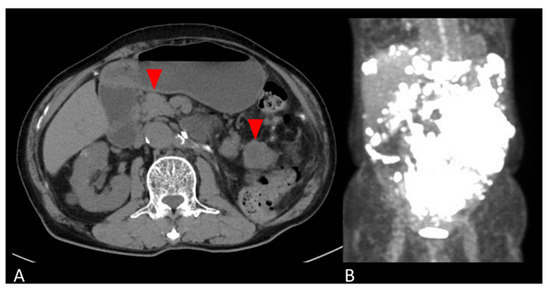

2. Case Presentation

2.1. Clinical Summary